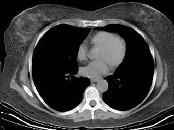

问题 女性患者,60岁,心房纤颤史5年,彩超提示房间隔占位,CT示房间隔见一椭圆形低密度影,CT值约为一300HU,边缘清楚,首先考虑为 ( )

选项 A、房间隔缺损 B、心脏转移瘤 C、淀粉样变 D、脂肪瘤 E、血栓

答案 D